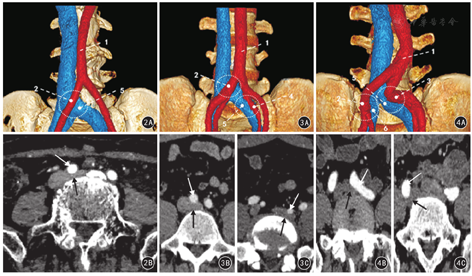

Ⅰ型,左髂总静脉单一压迫;Ⅱ型,左髂总静脉双重压迫;Ⅲ型,左右髂总静脉双侧压迫;Ⅳ型,其他压迫类型。

200例中各分型占比:Ⅰ型20.5%(41/200)、Ⅱ型36.5%(73/200)、Ⅲ型23.5%(47/200)、Ⅳ型19.5%(39/200)。见图2,图3,图4。各分型中占比最高的压迫类别:右髂总动脉压迫左髂总静脉占78.0%(32/41);左、右髂总动脉同时压迫左髂总静脉占72.6%(53/73);左、右髂总动脉同时压迫左髂总静脉伴右髂总动脉压迫右髂总静脉占27.7%(13/47);右髂总动脉压迫左髂总静脉伴左髂总动脉压迫左髂外静脉占30.8%(12/39)。Ⅰ~Ⅳ型髂静脉压迫者不同年龄段、性别、不同狭窄率间比较差异均无统计学意义(χ2值分别是1.396、0.716、5.907,P值均>0.05),压迫点个数比较差异有统计学意义(χ2=223.438,P<0.01),见表5。

注:上排为容积再现(VR)图像;下排为对应上图压迫部位的CT增强扫描动脉期横断面图像;红色为动脉,蓝色为静脉,圆圈为压迫部位;1为腹主动脉;2为右髂总动脉;3为左髂总动脉;4为左髂内动脉;5为左髂总静脉;6为右髂总静脉